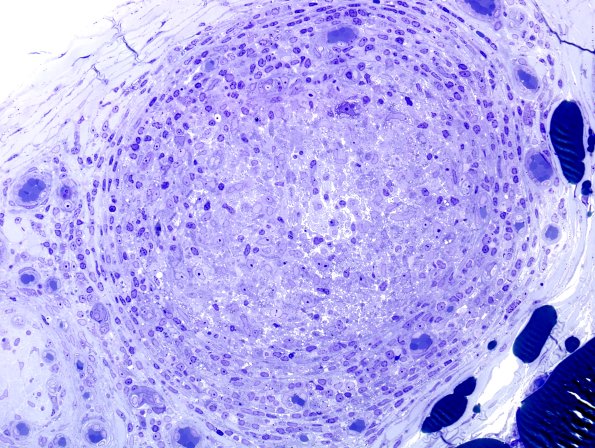

6A6 Leprosy, tuberculoid (Case 6) Plastic 12

This fascicle is dominated by epithelioid histiocytes. (Plastic section)